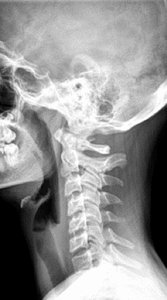

FIG 3 Lateral cervical view revealing a straight cervical spine.

I then looked at her X-rays. The most important view is the A-P L-S. We took the first series barefoot. On this view, I first looked at femoral head height. She had a 6.8 mm femoral head height difference, higher on the right. (Fig. 2) On her lateral L-S view, she had a lumbarization, removing the ability to know exactly what her Ferguson's center of gravity showed, as well as her sacral base angle. On lateral cervical (Fig. 3), she had a straight cervical spine, often associated with chronic headaches. The open-mouth view (Fig. 4) showed the significant imbalance between atlas and axis.